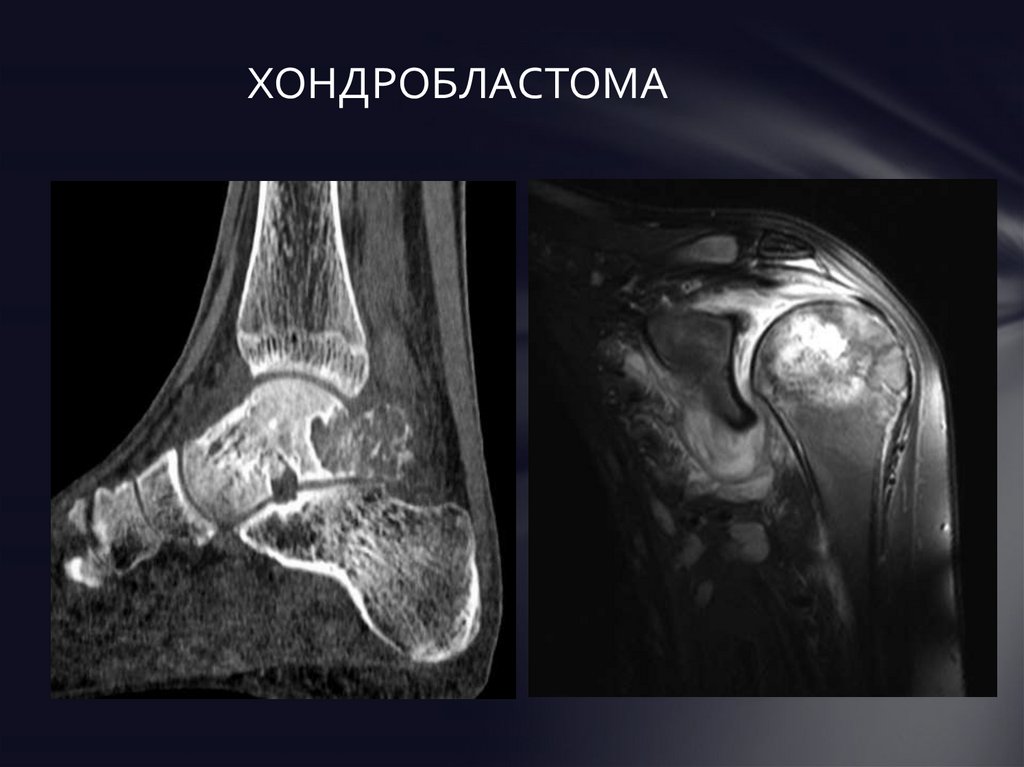

Рентгеновские снимки доброкачественных опухолей костей